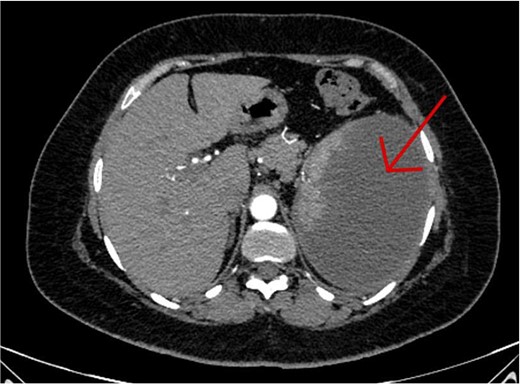

The CT scan confirmed a Dieulafoy’s lesion from the left phrenic artery (Fig. 2a and b) and showed collateral vascular channels around the pancreas with near-complete celiac trunk compression by the median arcuate ligament (Fig. 3). She underwent left phrenic artery embolization without complications, while asymptomatic celiac artery compression was treated conservatively. A follow-up endoscopy showed no bleeding or ulcers (Fig. 1d). Later, she developed severe left flank pain, and a contrast-CT revealed splenic vein thrombosis with infarction (Fig. 4), which was treated conservatively. Additionally, an incidental finding of left pleural effusion was drained. Rising inflammatory markers were managed with analgesics and IV antibiotics. She was discharged with outpatient follow-up, and at her 10-day visit, she reported improvement, stable hemoglobin, and normal inflammatory markers. She was satisfied, and a follow-up endoscopy was planned in 2 weeks.

(a) Axial CT angio of the abdomen shows a small area of enlarged tortuous blood vessels seen along the posterior cardia of the stomach; these findings are suggestive of Dieulafoy lesion. (b) Coronal abdominal CT images show the feeding blood vessel arising from the descending abdominal aorta located just superior to the origin of the left renal artery.